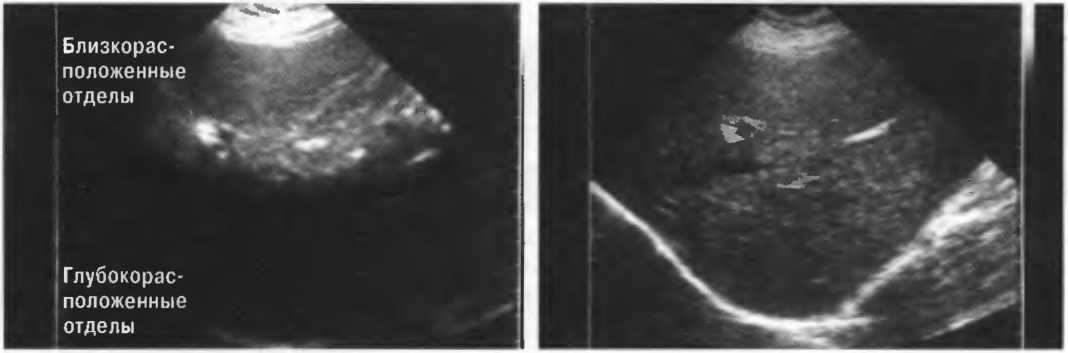

Усиление

Эхосигналы, отраженные от глубокорасположенных структур, являются более слабыми, чем те, которые идут от поверхностных структур; поэтому они должны быть усилены. В ультразвуковом аппарате есть устройство, компенсирующее затухание эхосигнала по глубине. Во всех ультразвуковых сканерах есть возможность изменять степень усиления и улучшать качество получаемого изображения (рис. 4).

Рис.4. На эхограмме слева усиление глубоких тканей слабое, поэтому от них нет отраженных сигналов. На правой эхограмме произведена коррекция чувствительности, и отраженные сигналы имеют одинаковую интенсивность по всей глубине.

Чувствительность и регулировка чувствительности прибора

Необходимо знать, что неправильная регулировка чувствительности может сделать диагностику неточной либо просто невозможной.

На эхограммах рис. 13 представлены различные варианты регулировки чувствительности и усиления по глубине.

Рис. 13а. Эхография печени. Слева: слишком слабое усиление глубоких отделов. Справа: слишком слабое усиление поверхностных отделов.

Рис.13б. Эхография печени. Слева: общее повышение чувствительности. Справа: общее понижение чувствительности.

Рис.13в. Эхография печени. Слева: слабое усиление срединных отделов печени, справа: правильная регулировка, усиление по глубине.